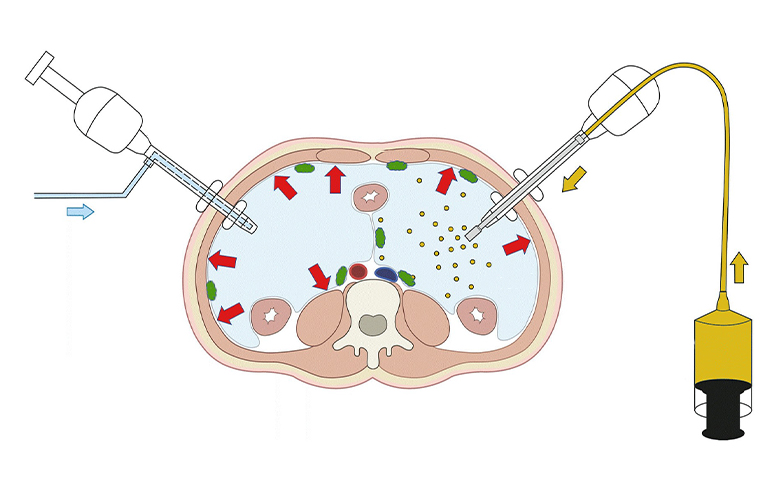

Detaylı BilgiPIPAC

PIPAC yönteminde kemoterapi ilaçları standart kemoterapiye benzer şekilde karın içine verilir ancak bu kez dozları damardan verilenlere göre 1/10 düzeyinde olur.